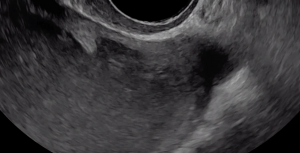

A hypoechoic deep endometriosis nodule is noted within the hyperechoic uterosacral ligament, infiltrating the parametrium

A hypoechoic deep endometriosis nodule is noted within the hyperechoic uterosacral ligament.

A hypoechoic deep endometriosis nodule is noted within the hyperechoic uterosacral ligament. In this case, there is an ovary containing an endometrioma fixed to the uterosacral ligament nodule.